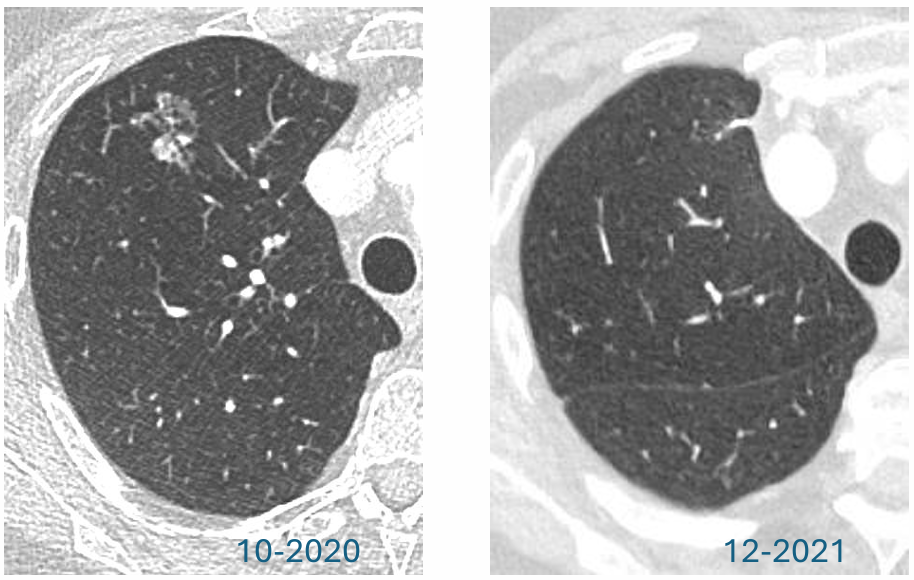

为明确该肺部结节性质,后续立即进行诊断性胸部CT扫描。2019年1月CT影像特征:CT(包括MIP重建)显示右肺上叶存在一个形态不规则的复杂结节。结节为亚实性病变,总直径长达19mm。关键风险特征:病灶包含一个直径大于8mm的实性成分。根据多项国际肺结节处理指南(如BTS、Fleischner指南)以及LungRADS 1.1(评分为4A/X类),直径>15mm或实性成分>8mm的亚实性结节,均被评估为高度可疑的恶性病变,需要立即进行诊断性检查(如活检)或密切的短期随访(如3-6个月复查)。

sVUCgSwlFnEPUOJ9TygVZNOIE0tcpvlD.png